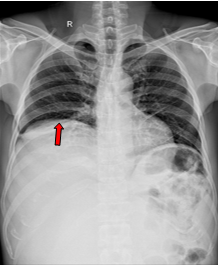

Hình ảnh chụp chụp cắt lớp vi tính ổ bụng sau phẫu thuật 1 tuần (03/2025): Hình ảnh sau mổ u sau phúc mạc bên phải, hiện thấy tụ dịch-khí khoang sau phúc mạc kèm ống dẫn lưu bên trong. Khí tự do ổ bụng (sau mổ). Khí trong mạc treo ruột. Dịch tự do ổ bụng

Hình 3. Hình ảnh chụp cắt lớp vi tính ổ bụng: Hình ảnh sau mổ u sau phúc mạc bên phải, hiện thấy tụ dịch-khí khoang sau phúc mạc  (sau mổ 1 tuần)